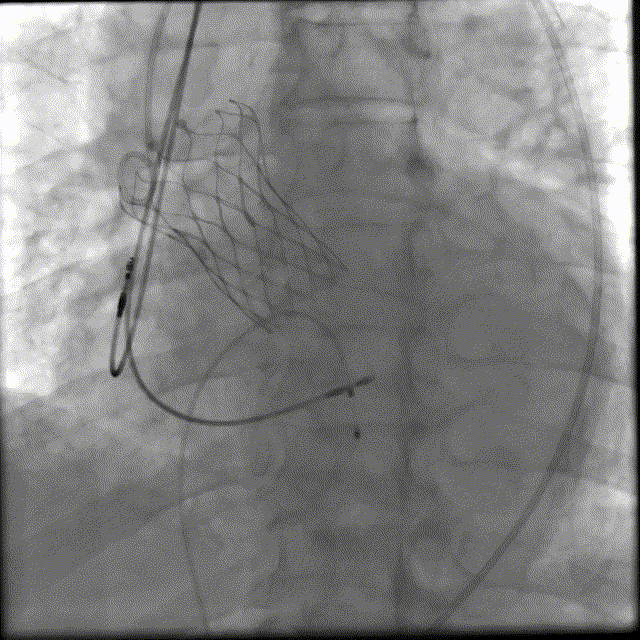

3. 在J型导丝指引下,使用6F pigtail造影导管进入左心室,测得主动脉瓣跨瓣压差15mmHg, 升主动脉血压180/40mmHg, 左心室压力165/5mmHg, 交换为特硬导丝Lunderquist至左心室,结合术前冠脉CT和心脏超声测量的瓣环直径大小,选择VitaFlow Liberty™30可回收瓣膜系统送至主动脉瓣环处,在Pigtail导管定位,主动脉根部造影协助指导下,精准定位,以180次/分快速起搏,逐步释放瓣膜,支架释放后退出导管输送系统,猪尾导管行主动脉根部造影示:人工瓣膜深度4mm, 冠状动脉开口未受影响,食道超声提示无主动脉瓣反流。

4. 复查造影示瓣膜支架开放良好,无瓣周漏,升主动脉血压恢复至150-160/70-75mmHg。拔出临时起搏电极,退出导管鞘后示左右股动脉无出血,使用Proglide缝合器进行双侧血管缝合,造影示左、右股动脉无出血、夹层、狭窄。

释放后造影